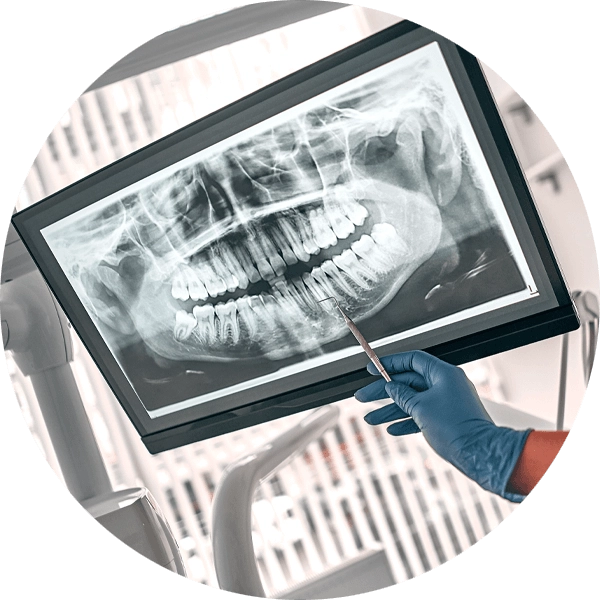

The decision to perform an extraction is typically straightforward when a tooth is affected by significant decay, severe periodontal disease, or a fracture. Digital X-rays are used to analyze the underlying structures and determine if the tooth can be saved. If there is a pulp infection without a tooth fracture, root canal therapy is a highly successful method for preventing extraction.

During your initial consultation at Kari Mann Dental Studio in Cape Coral, FL, we'll determine if tooth extraction is needed based on your oral exam, symptoms, and diagnostic imaging. We accept insurance from several leading insurance providers and offer financing to make paying for extraction as painless as possible. If we decide tooth extraction is the best option, you'll schedule this appointment before leaving our office.